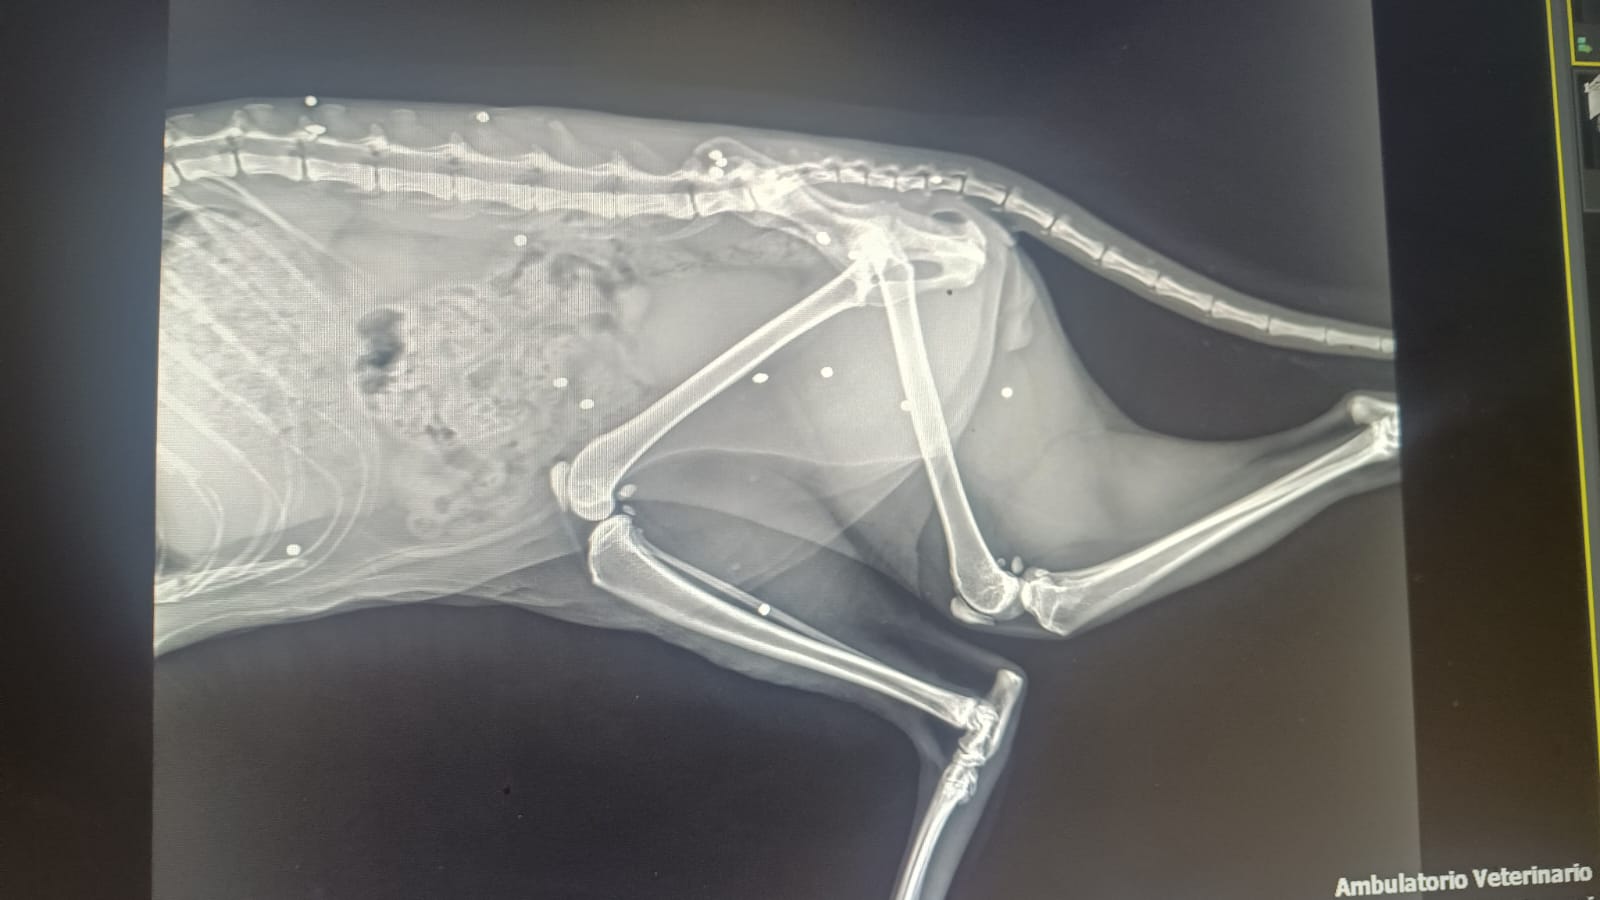

Leo è riapparso domenica 26 ottobre. Quando la signora ha aperto la porta di casa si è trovata ai piedi il piccolo animaletto "in condizioni pietose: ridotto a pelle ed ossa, sporco di fango, con dei grumi di sangue dappertutto, sfinito, impaurito che ha alzato il musino e la guardava". Portato immediatamente dalla veterinaria, la dottoressa non ha avuto dubbi: "La radiografia ha confermato che al piccoletto era stata sparata una fucilata in volto e tanti pallini di piombo erano penetrati nella testa e nel corpo e per questo motivo Leo sarebbe rimasto cieco". Nella mattina di giovedì 30 ottobre, l'uomo autore del post ha incontrato la signora, che aveva Leo nel trasportino: "La veterinaria mi ha confermato che da un occhio non vedrà mai più mentre dall’altro c’è una flebile speranza, una volta guarito l’edema cerebrale, potrebbe riacquistare un po' di vista. Adesso, dopo diverse cure, si sta riprendendo e poco alla volta rafforzando". E' stata sporta denuncia ai carabinieri forestali, che indagheranno per cercare di far luce su quanto accaduto.